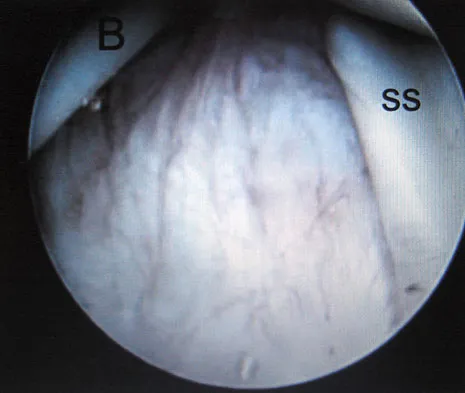

A 40-year-old man has a palpable mass over the dorsum of the ankle. He reports no history of direct trauma but notes that he sustained a laceration to the middle of his leg 6 weeks ago. Examination reveals a 4-cm x 1-cm mass. T1- and T2-weighted MRI scans are shown in Figures 12a and 12b. An intraoperative photograph and biopsy specimen are shown in Figures 12c and 12d. What is the most likely diagnosis?

Explanation